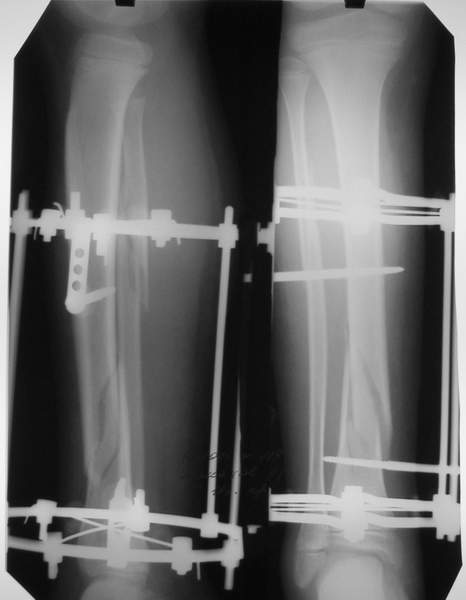

В аттачтах №№ 1 и 2 - примеры, когда 2 кольца не позволили послеоперационно

исправить смещение фрагментов большеберцовой (по ширине и вальгусное).

А казалось бы (#2) - поиграй на штангах и все влетит.

Оперировал не я

:-)

1

1a